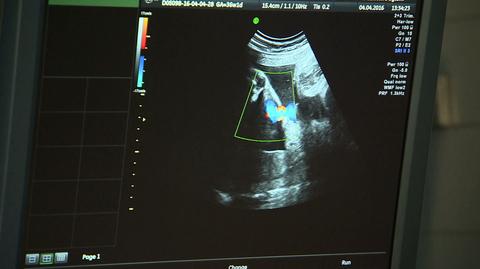

Kobieta w ciąży, która nie zaszczepiła się przeciw COVID-19, naraża na ciężką chorobę siebie i swoje dziecko lub dzieci. Do Centrum Zdrowia Matki Polki w Łodzi trafiają chore na COVID-19 kobiety w ciąży. - Dziewczyny są chore, w ciężkim stanie. Ich dzieci są w bardzo ciężkim stanie. No, nie chciałabym być w grupie tych mam, które się muszą martwić o własne dziecko. Jeżeli matka kocha swoje dzieci, na pewno się zaszczepi - uważa Milena Rozpędowska, matka bliźniaczek.

Kolejny noworodek urodził się zakażony koronawirusem. Zastosowano cesarskie cięcie przed czasem, bo stan chorej na COVID-19 matki był zbyt ciężki, by ryzykować życie obojga. Na szczęście pomoc przyszła na czas. Dla obojga.

- Część tych problemów wynikała na pewno z wcześniactwa, chociażby taki klasyczny zespół zaburzenia oddychania, ale też zmiany zapalne jednak w płucach - mówi profesor Ewa Gulczyńska, kierowniczka Kliniki Neonatologii w Instytucie Centrum Zdrowia Matki Polki w Łodzi. Gdyby mama się zaszczepiła, można byłoby uniknąć jednego i drugiego.